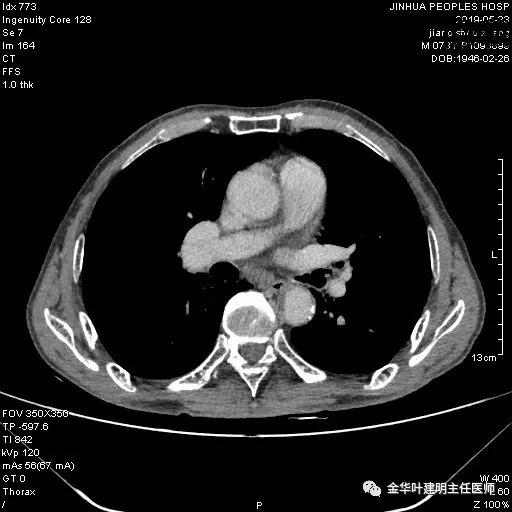

考虑左侧大量胸腔积液,遂进一步胸部CT检查:

以上是肺窗表现,下面为纵隔窗影像: